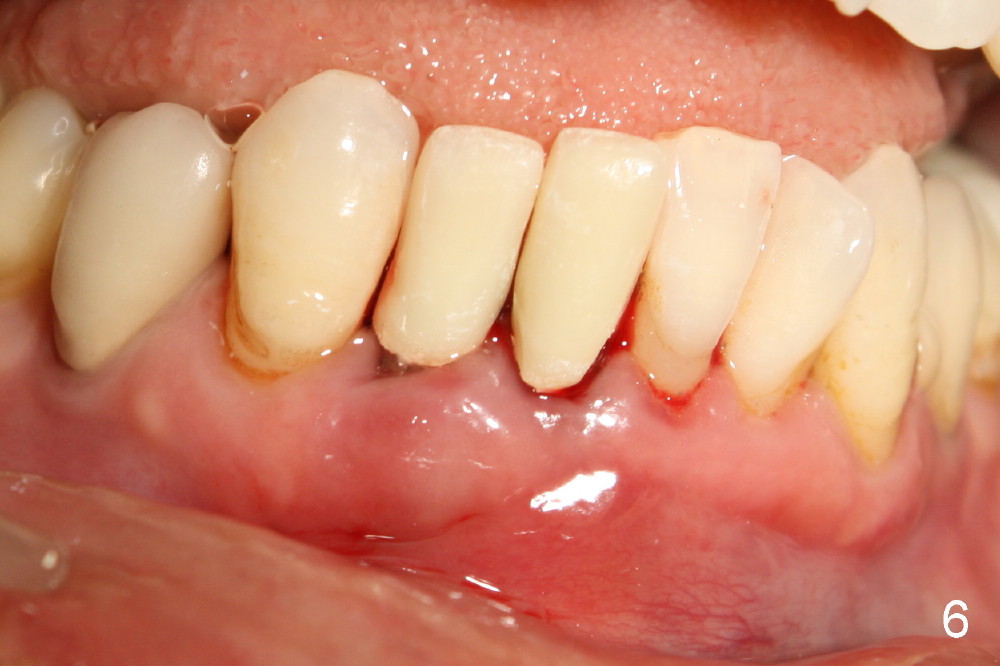

A 60-year-old lady wants to remove 2 mobile lower right incisors (Fig.1,2; with infection at the lateral (>)). Immediate 1-piece implants are placed (Fig.3,4): 3x17 mm at the central, 3.5x17 mm at the lateral. Insertion torque is > 60 Ncm for the implants. No bone graft is placed. After prep (Fig.5), two separate provisionals are fabricated (Fig.6). The one at the lateral incisor looks bulky at the cervix, because of the oversized implant for the site (over-engineering). Use of smaller implant (3.0 (instead of 3.5), 2.5 (instead of 3.0) or 2.0 mm) may solve the problem. Seven days postop, the infection resolves (Fig.7 >) with normal-looking papilla (*).